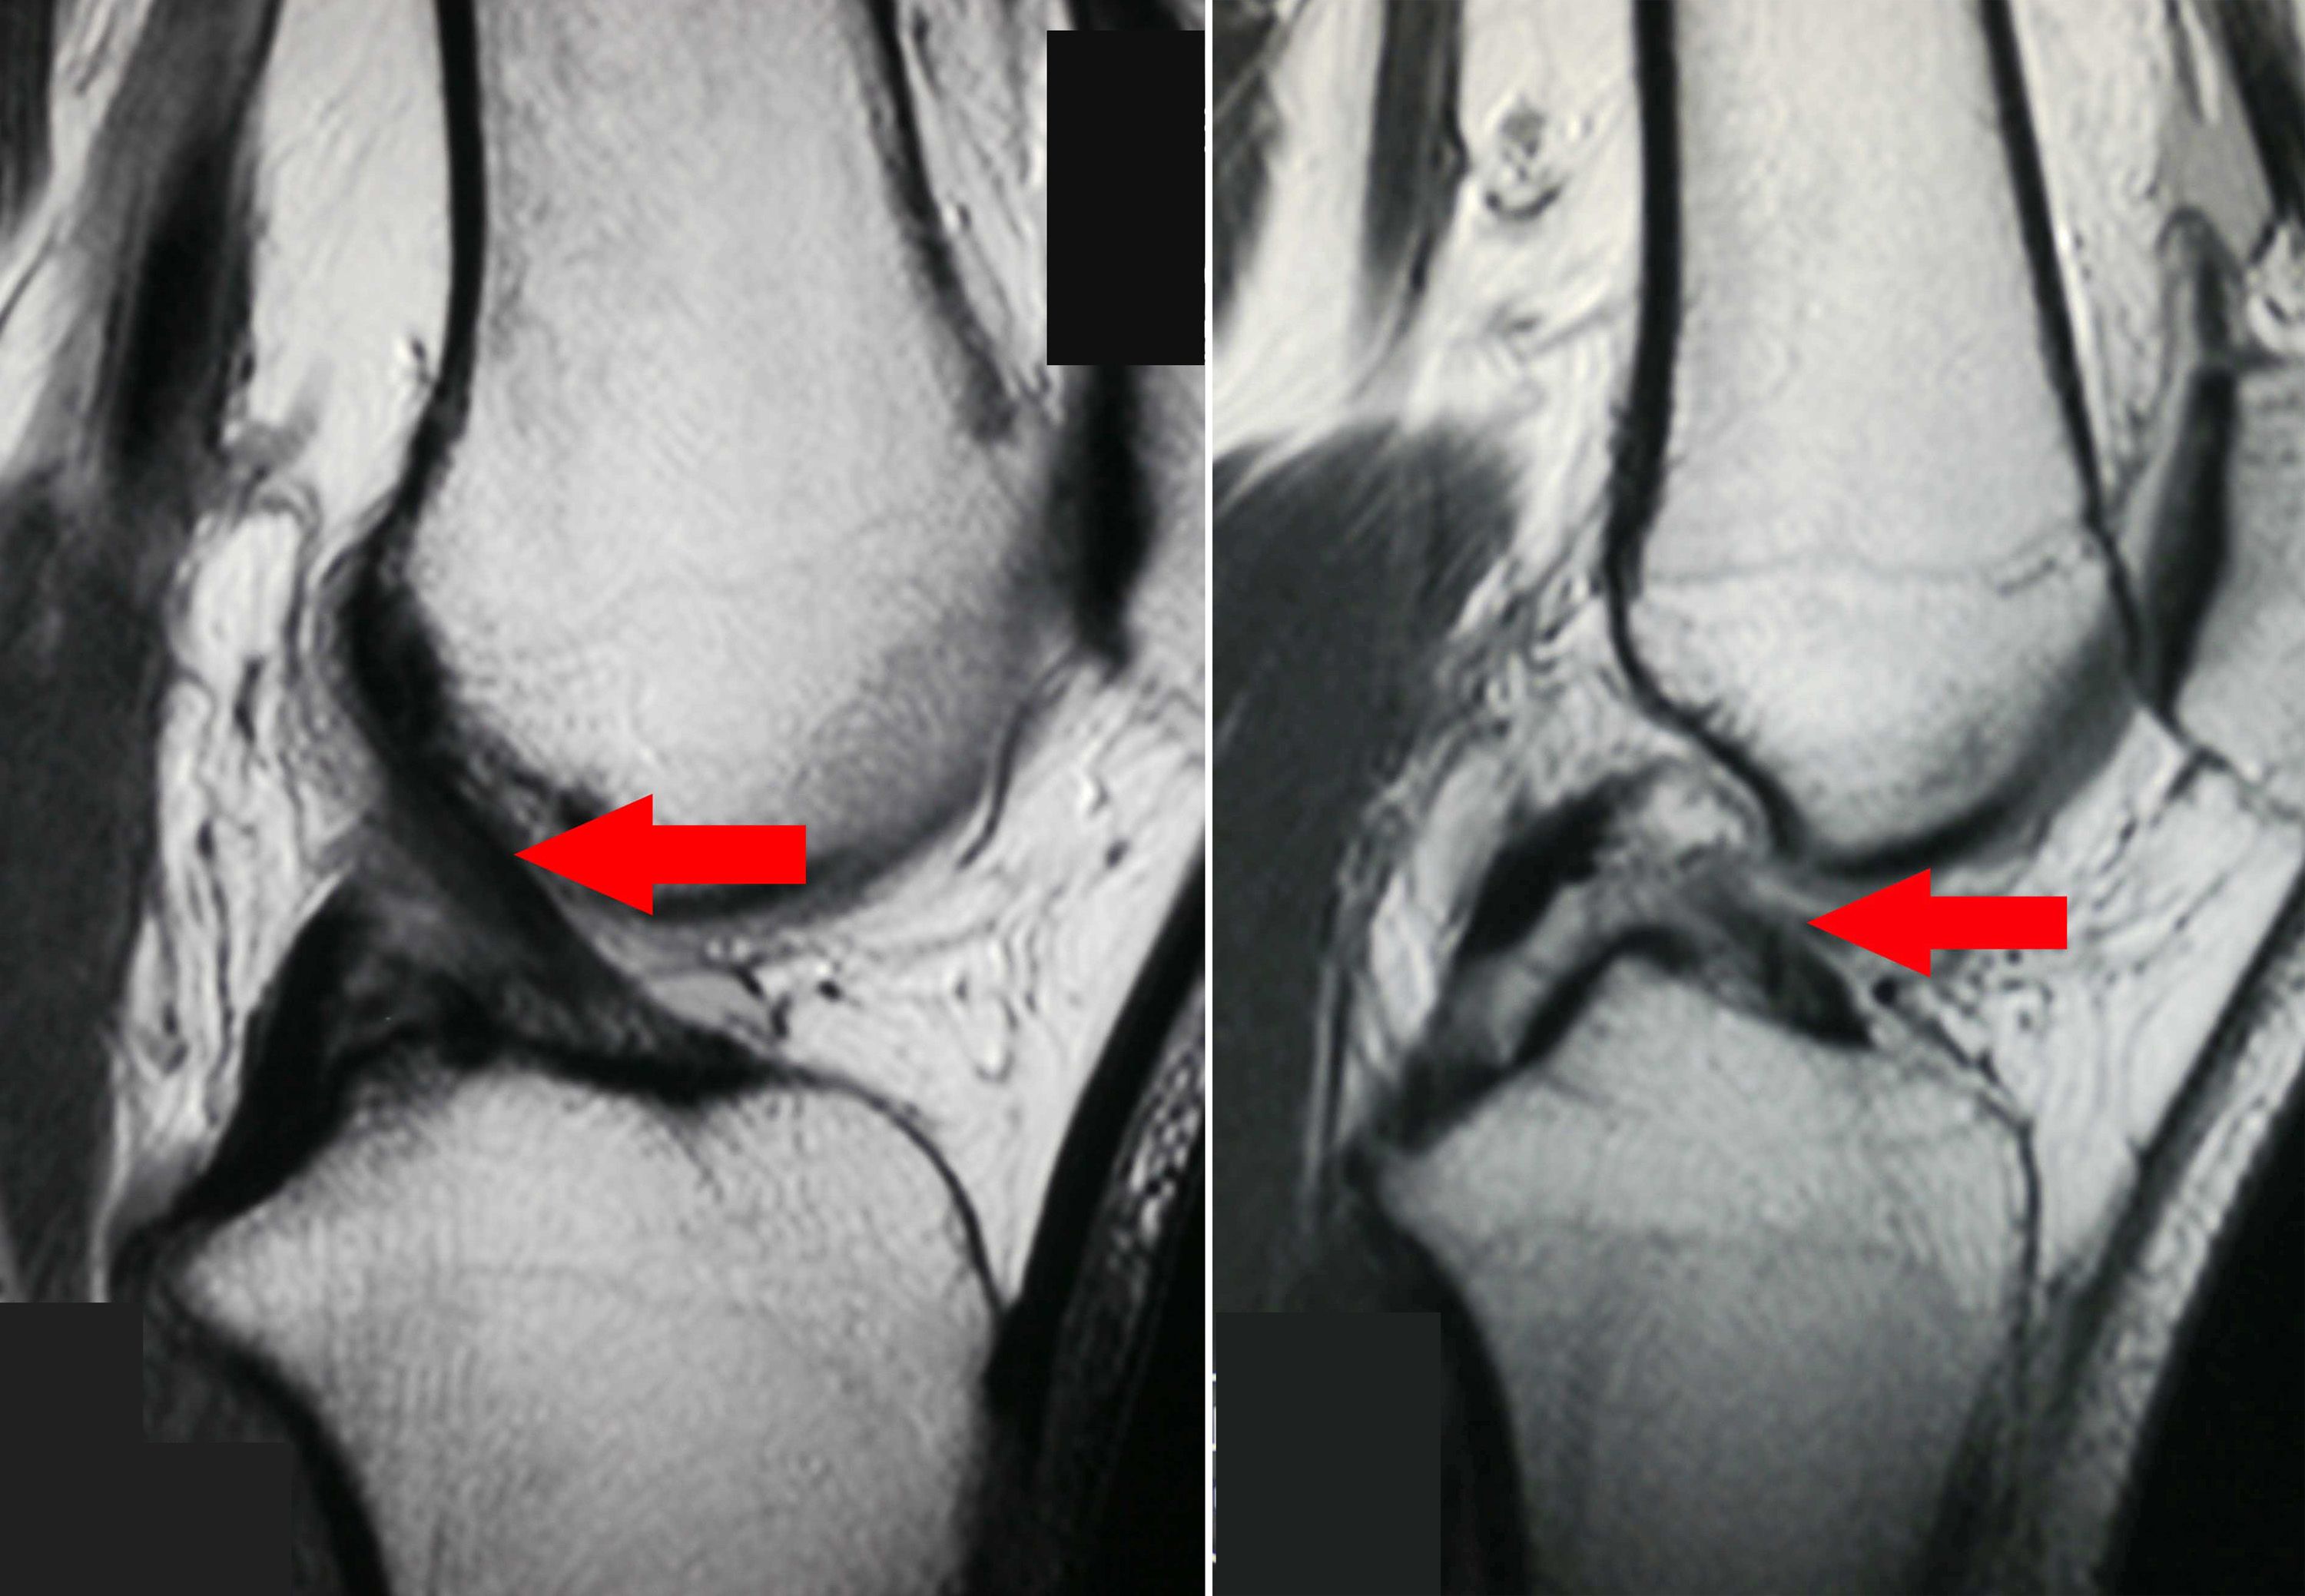

(Izquierda)  Esta imagen de IRM de una rodilla tomada desde el costado muestra un ligamento cruzado anterior saludable. (Derecha) Esta IRM muestra un ligamento cruzado anterior desgarrado, lo que hay causado inestabilidad en la rodilla del paciente.

Una IRM puede usarse para ayudar a diagnosticar ligamentos y cartílagos de rodilla desgarrados, manguitos rotadores quebrados, hernias de disco, osteonecrosis, tumores óseos y otros problemas. El estudio puede demorar de 30 a 60 minutos. Al igual que una TC, una IRM puede realizarse en un hospital o un centro de diagnóstico por imágenes en forma ambulatoria.